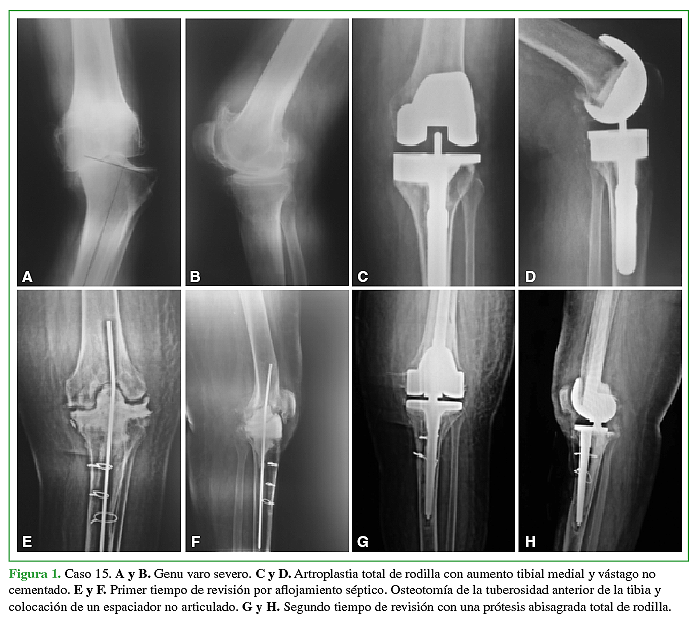

Artroplastia total de rodilla en pacientes con secuela de fracturas articulares. Resultados del seguimiento a mediano plazo

Acceso mediante suscripción PDF Acceso mediante suscripción PDF_EN (English) Acceso mediante suscripción HTML Acceso mediante suscripción Figura 1 (a-c) Acceso mediante suscripción Figura 1 (d-e) Acceso mediante suscripción Figura 1 (f) Acceso mediante suscripción Tabla 1 Acceso mediante suscripción Tabla 2 Acceso mediante suscripción Tabla 3 Acceso mediante suscripción Tabla 4